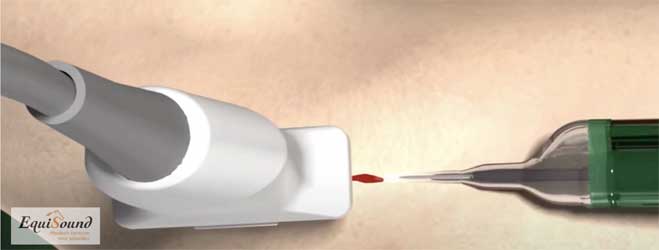

Tenex is een behandelingstechniek die 5j geleden ontwikkeld werd in USA om chronische peesaandoeningen te behandelen bij mensen (chronische achillespezen, hielspoor, patellapeesdegeneratie etc). De techniek maakt gebruik van ultrason geluid (zoals bij het verwijderen van tandsteen) om beschadigd weefsel af te breken en zo het genezingsproces te stimuleren en een nieuwe herstelkans te geven. De geluidsfrequentie is specifiek gekozen om enkel harde weefsels (fibrose en mineralisaties) af te breken en geen schade aan te brengen aan gezond peesweefsel. De ultrason behandeling wordt toegediend door middel van een holle naald in een holle buis (zie foto 9a). Uit de holle naald komt tijdens de behandeling een influx van NaCl dewelke tegelijk geaspireerd wordt door de holle buis (foto 9b en 9c). Het water zorgt in eerste instantie voor de afvoer van gedebrideerd weefsel, maar tegelijk ook voor afkoeling van de naald dewelke erg opwarmt door het ultrason proces.